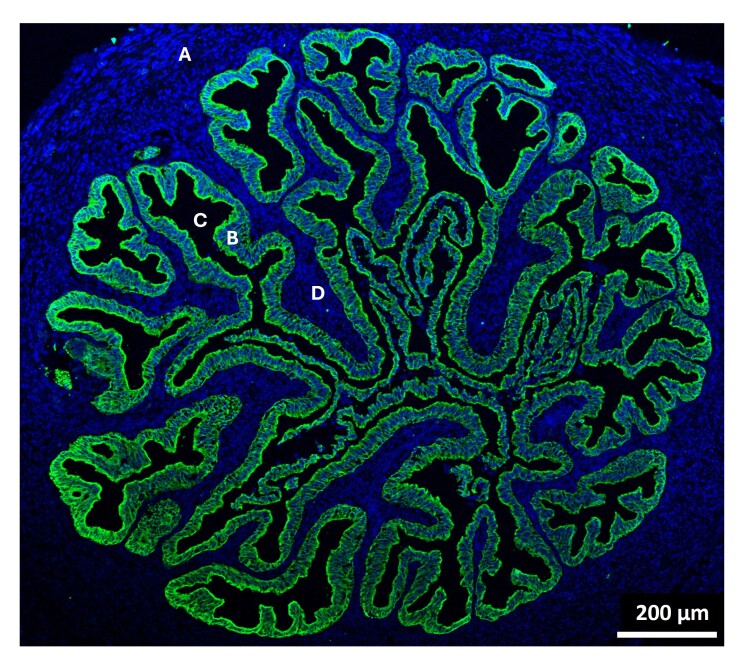

本文综述了输卵管在围感期的作用和潜在机制的最新综述。重点介绍了受精前、受精中和受精后输卵管的功能,重点介绍了上皮细胞接触和输卵管分泌物对精子选择机制和受精能力获得的影响。本文还提供了目前关于输卵管如何通过整体物理环境(氧张力、流体电流、纤毛上皮细胞)及其分泌物的作用来支持受精和胚胎发育的知识。总之,这篇综述强调了输卵管在配子选择和早期胚胎发育中的独特作用,到目前为止,当使用辅助生殖技术(ART)时,这还不完全可能反映出来。揭示输卵管分泌物最重要的功能成分有助于更好的精子选择,提高精子受精能力和早期胚胎发育,确实有助于改善目前用于抗逆转录病毒治疗的体外系统的结果。

This review provides an up-to-date overview of the roles of the oviduct during the periconception period and underlying mechanisms. The functions of the oviduct before, during, and after fertilization are highlighted, with special focus on the effects of epithelial cell contact and luminal secretions on sperm selection mechanisms and acquisition of fertilization ability. The current knowledge on how the oviduct contributes to support fertilization and embryo development via the overall physical milieu (oxygen tension, fluid current, ciliated epithelial cells) and the role of its secretions is also provided. Altogether, the review underlines the unique role of the oviduct during gamete selection and early embryo development, which so far has not been completely possible to mirror when assisted reproductive technologies (ART) are used. Unveiling the most important functional components of oviductal secretions that contribute to better sperm selection, and boost sperm fertilizing ability and early embryo development, can indeed be useful to improve the outcomes of current in vitro systems used in ART.